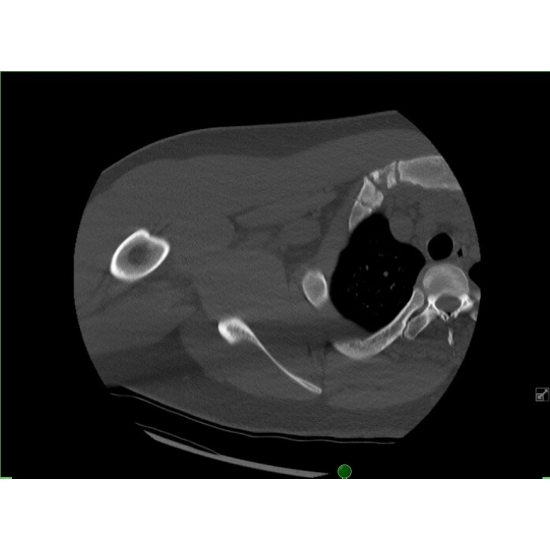

| Battered And Bruised: A Rare Cause Of Thoracic Pain In A Division One Offensive Lineman - Page #3 | |||